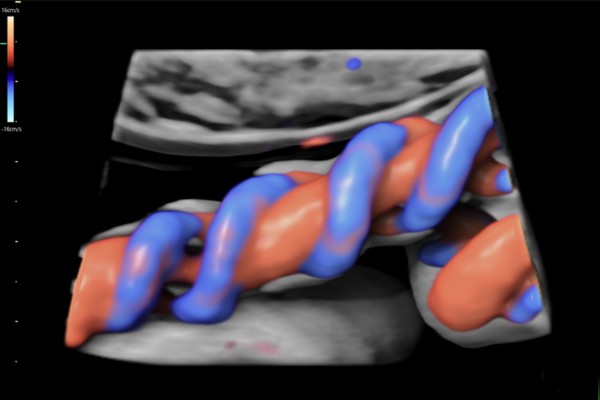

Doppler Placentario

Examina el flujo sanguíneo en la placenta y cordón umbilical, fundamental para detectar insuficiencia placentaria y garantizar la correcta nutrición del bebé.

Doppler Arterias Uterinas

Evalúa el flujo en las arterias uterinas para predecir riesgo de preeclampsia, restricción del crecimiento fetal y otras complicaciones del embarazo.